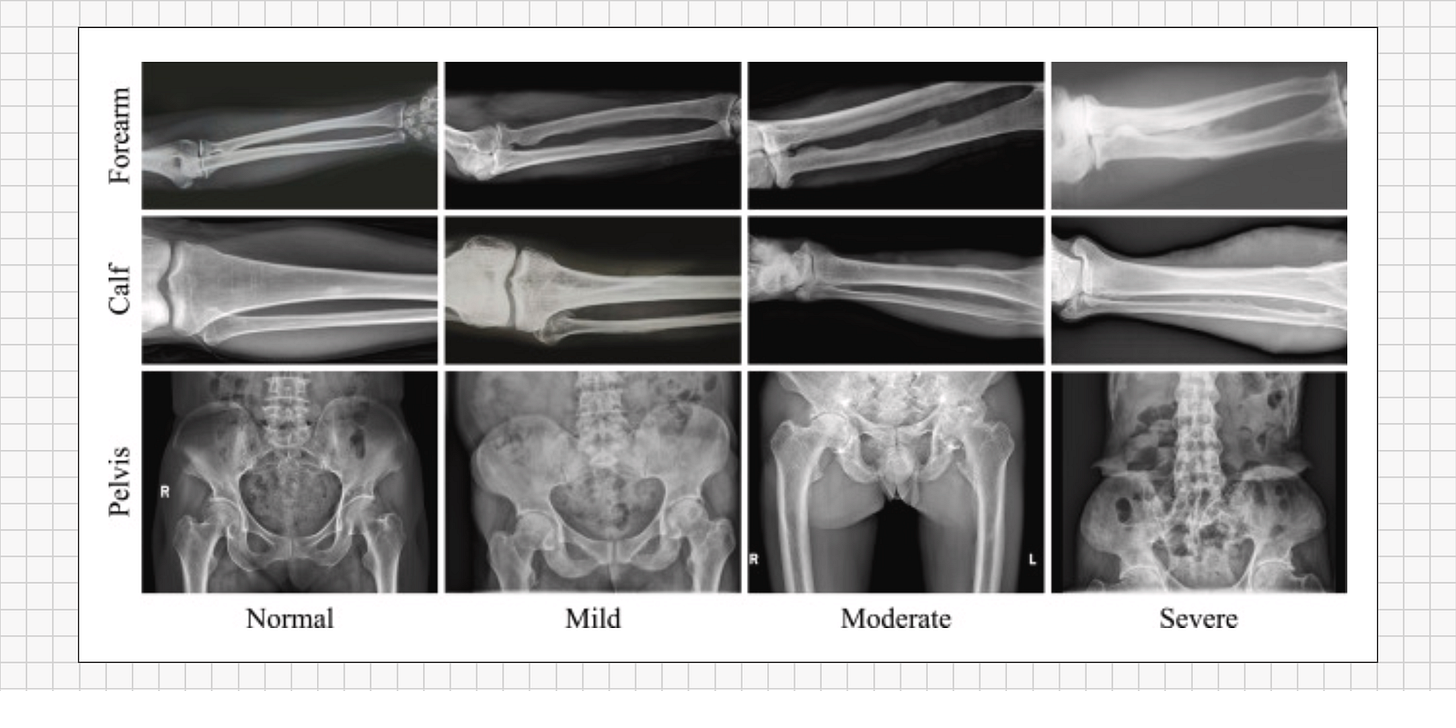

Fluoride’s harmful effects on bone don’t happen overnight - they build up gradually over decades. As more and more fluoride accumulates in the skeleton, skeletal fluorosis typically progresses through several stages of increasing severity:

Early Stage (Mild): Vague aches and stiffness begin to appear, often in the lower back, hips, knees, or neck. At this stage, someone might notice occasional joint pain or a stiff back, especially in the morning or after exercise. These subtle symptoms are easily mistaken for normal aging or everyday wear-and-tear. There are usually no obvious signs on X-rays yet, and bone density might even appear normal or only slightly increased.

Middle Stage (Moderate): With continued fluoride exposure, the symptoms become more pronounced and harder to ignore. Pain in the bones and joints grows more frequent, and movements that used to be easy – like bending, lifting, or climbing stairs – become increasingly difficult due to stiffness and pain. Ligaments and joint capsules may start to calcify (harden with mineral deposits), reducing flexibility. A person in this stage might have constant joint and back pain that doesn’t respond well to typical treatments. An X-ray at this point might show unusually dense bone patches or calcified ligaments around joints, although doctors might not immediately recognize these as signs of fluorosis.

Advanced Stage (Severe): After many years (often decades) of high fluoride accumulation, the damage can become crippling. Bones may thicken, deform, or develop odd bony outgrowths (exostoses). Joints can lose almost all mobility – for example, spinal vertebrae may enlarge and fuse together, and ligaments (especially in the spine and major joints) can ossify (literally turn to bone). The skeletal structure becomes so rigid that normal movement is profoundly limited. These changes can also compress nerves; for instance, hardened ligaments in the spine may pinch spinal nerves, leading to neurological symptoms like tingling, numbness, or weakness in the limbs. Muscles may waste away from disuse when movement becomes too painful or difficult. In extreme cases, a person may become nearly immobile – a condition historically known as crippling skeletal fluorosis. (In clinical reports, advanced fluorosis has led to patients becoming wheelchair-bound or bedridden due to multiple fractures and fused joints.)